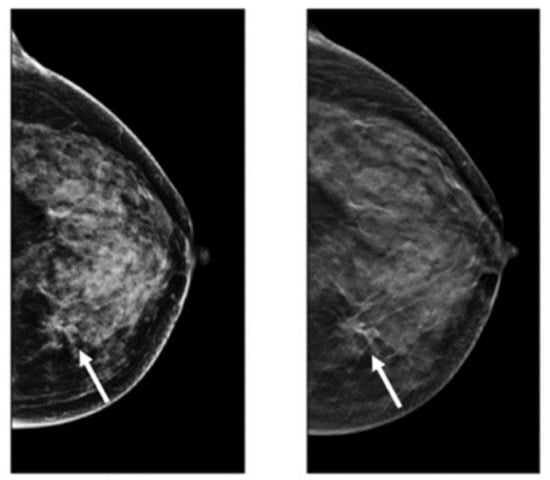

2.2. Digital Breast Tomosynthesis (DBT)

DBT is a novel imaging modality making 3D images of breasts by the utilization of X-rays captured from different angles [50]. This method is similar to what is performed in mammograms, except the tube with the X-ray moves in a circular arc around the breast [51,52,53] (Figure 2). Repeated exposures to the breast tissue at different angles produce DBT images in half-millimeter slices. In this method, computational methods are utilized to collect information received from X-ray images to produce z-stack breast images and 2D reconstruction images [53,54]. In contrast to the conventional FSM method, DBT can easily cover the imaging of tumors from small to large size, especially in the case of small lesions and dense breasts [55]. However, the main challenging issue regarding the DBT is the long reading time because of the number of mammograms, the z-stack of images, and the number of recall rates for architectural distortion type of breast cancer abnormality [56]. After FFDM, DBT is the commonly used method for imaging modalities. Many studies recently used this imaging modality for breast cancer detection due to its favorable sensitivity and accuracy in screening and producing better details of tissue in breast cancer [57,58,59,60]. Table 1 provides details of the pros and cons of DBT for breast cancer analysis.

Figure 2.

Images of cancerous breast tissue by DBT imaging modality [61]. Reprinted/adapted with permission from [61]. 2021, Elsevier.